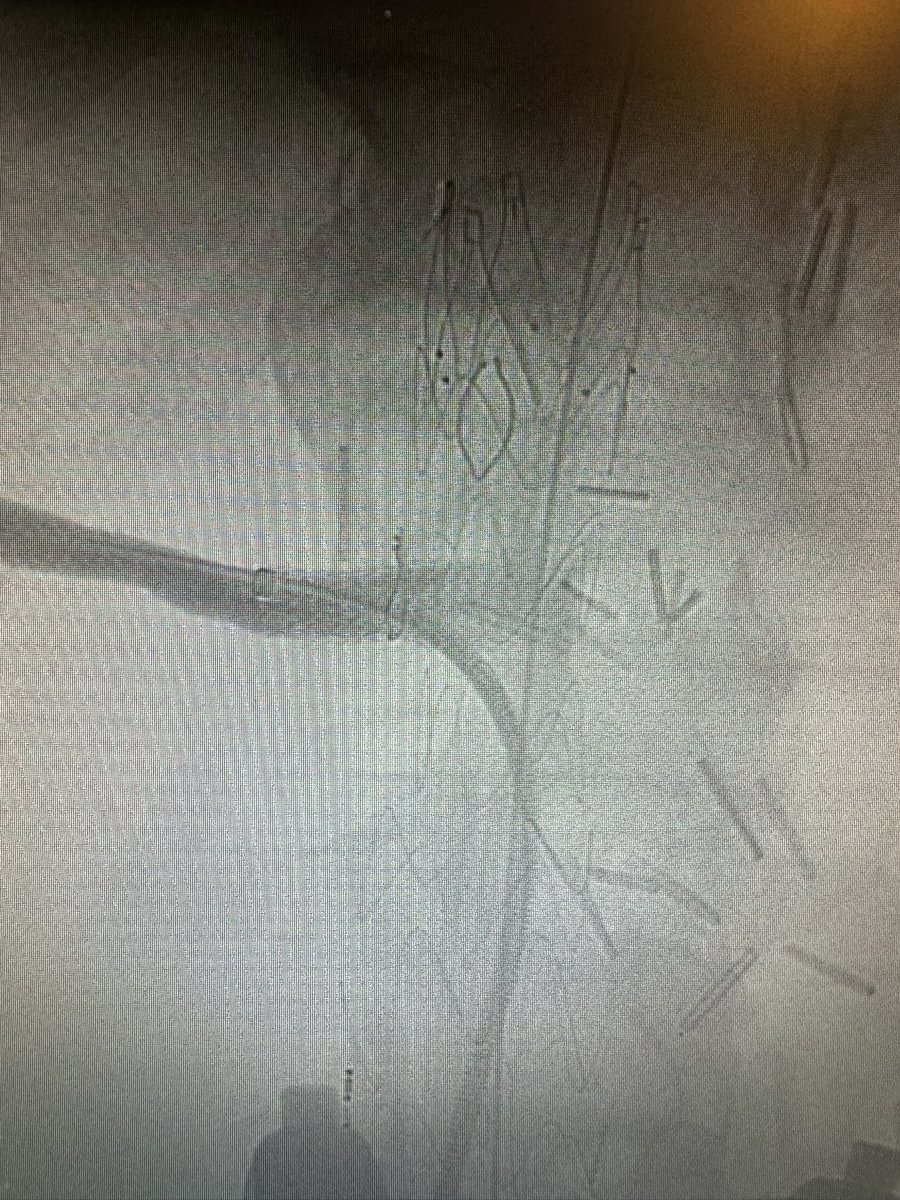

Two “firsts” at UW today, October 3rd, 2024: The 1st EVER TREO FIT PMEG in the world: Graft Modification Time 24 min, Fluoro Time 10.9 min, Procedure Time 49 min The 1st Fenestrated TREO CMD in the United States: Fluoro Time 18 min and Procedure